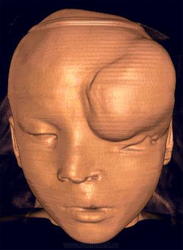

Передние черепно-мозговые грыжи вызывают обезображивание лица, деформацию глазниц, носа, при этом нередко отмечаются уплощенная широкая переносица, неправильное расположение глазных яблок, нарушение бинокулярного зрения. При назоорбитальных грыжах, как правило, выявляются деформация и непроходимость слезно-носового канала, часто развиваются конъюнктивит, дакриоцистит. Базальные черепно-мозговые грыжи, располагающиеся в полости носа или носоглотки, по внешнему виду напоминают полипы. Если грыжевой мешок находится в одной половине носа, возникает искривление носовой перегородки; при этом дыхание затруднено, речь невнятная с носовым оттенком.

Назоорбитальная (фронто-этмоидальная) грыжа.

Назо - этмоидальная грыжа.

Дополнительным признаком передних менингоцеле и грыж головного мозга является деформация лицевого скелета.

Назофронтальное менингожнцефалоцеле.

Передняя мозговая грыжа